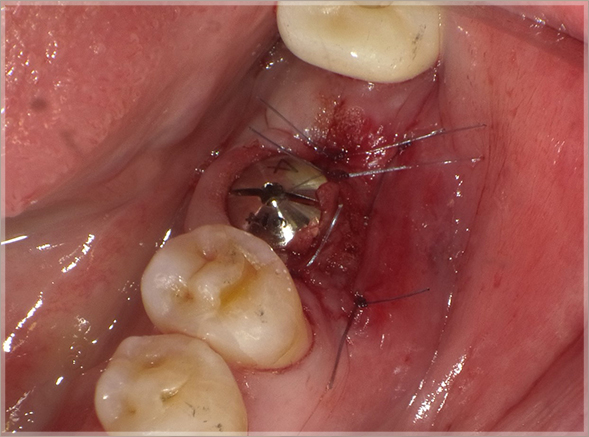

7.角化歯肉の安定を考慮した縫合をします

⑬初期固定値が高いので1回法インプラント治療としてテンポラリーヒーリングアバットメントを埋入と同時にセット、角化歯肉の安定を考慮して縫合する。